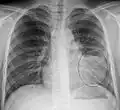

Normal AP CXR

AP CXR showing left lower lobe pneumonia associated with a small left sided pleural effusion -

AP CXR showing right lower lobe pneumonia -